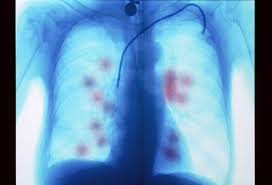

Symptoms Of Metastatic Lung Cancer In Dogs / Lung Cancer In Cats Symptoms Causes Diagnosis Treatment Recovery Management Cost - Dogs with lung cancer may not show any clinical symptoms in the early stage of the disease.. Primary surgical therapy with vatd should be considered for all patients with pleural empyema, irrespective of the duration of symptoms. For example, in the case of metastatic lung cancer in dogs, the tumor originates in the lungs and moves elsewhere throughout the body. Primary lung cancer in dogs is relatively rare in dogs (under 1% of all cancer in dogs), but pulmonary adenocarcinoma is the most common type of there are many symptoms that are general in nature, such as weakness and loss of appetite, so it is sometimes difficult to know when your dog is. Lung cancer in dogs can be primary or metastatic. The severity of signs depends on.

When cancer has spread to your lungs, treatment can help control and slow the growth of cancerous cells. Learn more in this article by moffitt cancer center. Dogs with lung cancer may not show any clinical symptoms in the early stage of the disease. Metastatic lung cancers (cancers that spread to the lungs from other locations) are much more common in dogs than primary lung cancers. Symptoms of metastatic disease (lungs, bones:

Metastatic lung cancer can cause symptoms in distant parts of the body. Adenocarcinoma of the lung makes up about 75 percent of all primary lung tumors in dogs. Metastases can occur in three ways Primary surgical therapy with vatd should be considered for all patients with pleural empyema, irrespective of the duration of symptoms. Search dog lung cancer symptoms, causes, and treatments at petmd.com. For instance, researchers hoping to reduce the risk of lung cancer in heavy smokers gave them beta carotene supplements. Metastatic cancer in dogs occurs when cancer has spread from its site of origination to other organs or tissues within the body. Lung cancer, also known as lung carcinoma, is a malignant lung tumor characterized by uncontrolled cell growth in tissues of the lung. It also helps you manage your symptoms so you. Virtually any type of malignant tumor has the possibility to spread to the dog's lungs, but some cancers are more likely. Learn about the common signs and symptoms of lung cancer such as a worsening cough, loss of appetite, or shortness of breath. The signs of metastatic lung disease are similar to those of primary lung tumors except that coughing is less common. Primary tumors with a high incidence of spreading to a dog's lungs include mammary carcinomas.

Among the symptoms of lung adenocarcinoma in dogs are: Jpn j clin oncol 1999; Cancer cells can spread (metastasize) to almost any other organ in the pet, commonly the lungs, bones or liver. Primary surgical therapy with vatd should be considered for all patients with pleural empyema, irrespective of the duration of symptoms. Most patients with lung cancer are symptomatic at the time of diagnosis. These have a lower rate of metastasis than nodular or diffuse tumors and are more easily removed, but without treatment, all the types of primary liver cancer can eventually metastasize to other parts of the body. Simptom clippings rigler (place of entry of the bronchus). Find out more about the causes, symptoms, and the treatment of this on the other hand, in metastatic lung cancer, the cancerous tumors develop somewhere else in the body, and then spread to the lung. This is a malignant neoplasm, with the ability to grow rapidly and metastasize to distant parts of the body, including the organs. Symptoms and treatments for metastatic lung cancer vary depending on where the new tumors appear, but with this process is called metastasis. Dogs with metastatic lung cancer are usually given less than 12 months to live, some treatments may increase the survival time, but generally not more than the protocol, or combination of protocols, will depend on the stage of the disease as well as, size, location, and whether metastasis has occurred. Metastatic lung cancers (cancers that spread to the lungs from other locations) are much more common in dogs than primary lung cancers. Primary lung cancer is rare but when it happens, it is often fatal.

Virtually any type of malignant tumor has the possibility to spread to the dog's lungs, but some cancers are more likely. Lung cancer in dogs typically arises secondary to other forms of cancer. Metastatic lung cancer cells have the same features as the original lung cancer cells. The signs of metastatic lung disease are similar to those of primary lung tumors except that coughing is less common. This growth can spread beyond the lung by the process of metastasis into nearby tissue or other parts of the body. Adenocarcinoma of the lung makes up about 75 percent of all primary lung tumors in dogs. Cancer cells can spread (metastasize) to almost any other organ in the pet, commonly the lungs, bones or liver. Unfortunately, their symptoms are often associated with locally advanced or distant specific signs and symptoms depend on the location of the tumor, its locoregional spread, and the presence of metastatic disease. These have a lower rate of metastasis than nodular or diffuse tumors and are more easily removed, but without treatment, all the types of primary liver cancer can eventually metastasize to other parts of the body. Among the symptoms of lung adenocarcinoma in dogs are: Symptoms of metastatic disease (lungs, bones: Metastases can occur in three ways Read on and find out more about the symptoms, causes, and conventional treatment of lung cancer in dogs.